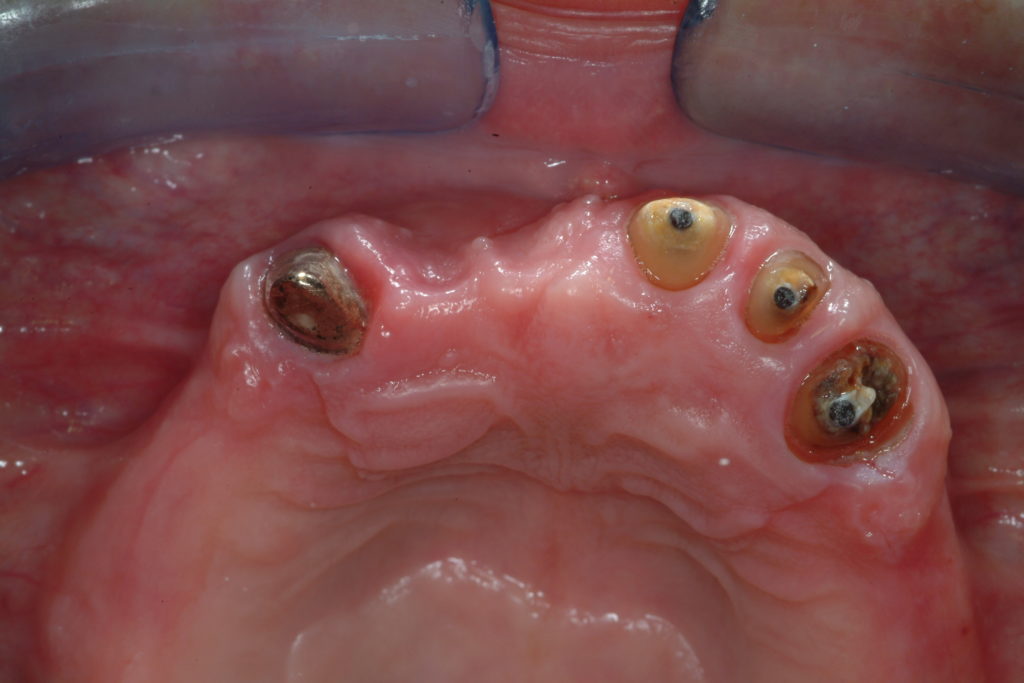

Multiple dental implants

The rules are the same as for single implants with the opportunities being immediate loading, post-extraction implants or immediate loading post-extraction implants.

Even in the case of multiple implants, patients can get a new, titanium root and even the tooth itself on the same day. In a single session we can replace the missing tooth with the implant and insert a temporary crown.

After a period of stabilization of the implant and healing of the gum, varying between 3 and 6 months, the final porcelain bridge is cemented or screwed. Comfortable chewing is recuperated, and patients can smile naturally.

The teeth are thus replaced without touching or damaging the adjacent teeth and without having to insert unnatural and uncomfortable removable prostheses. Furthermore, the thickness of the bone and the integrity of the facial tissue profile are maintained.

Clinical cases